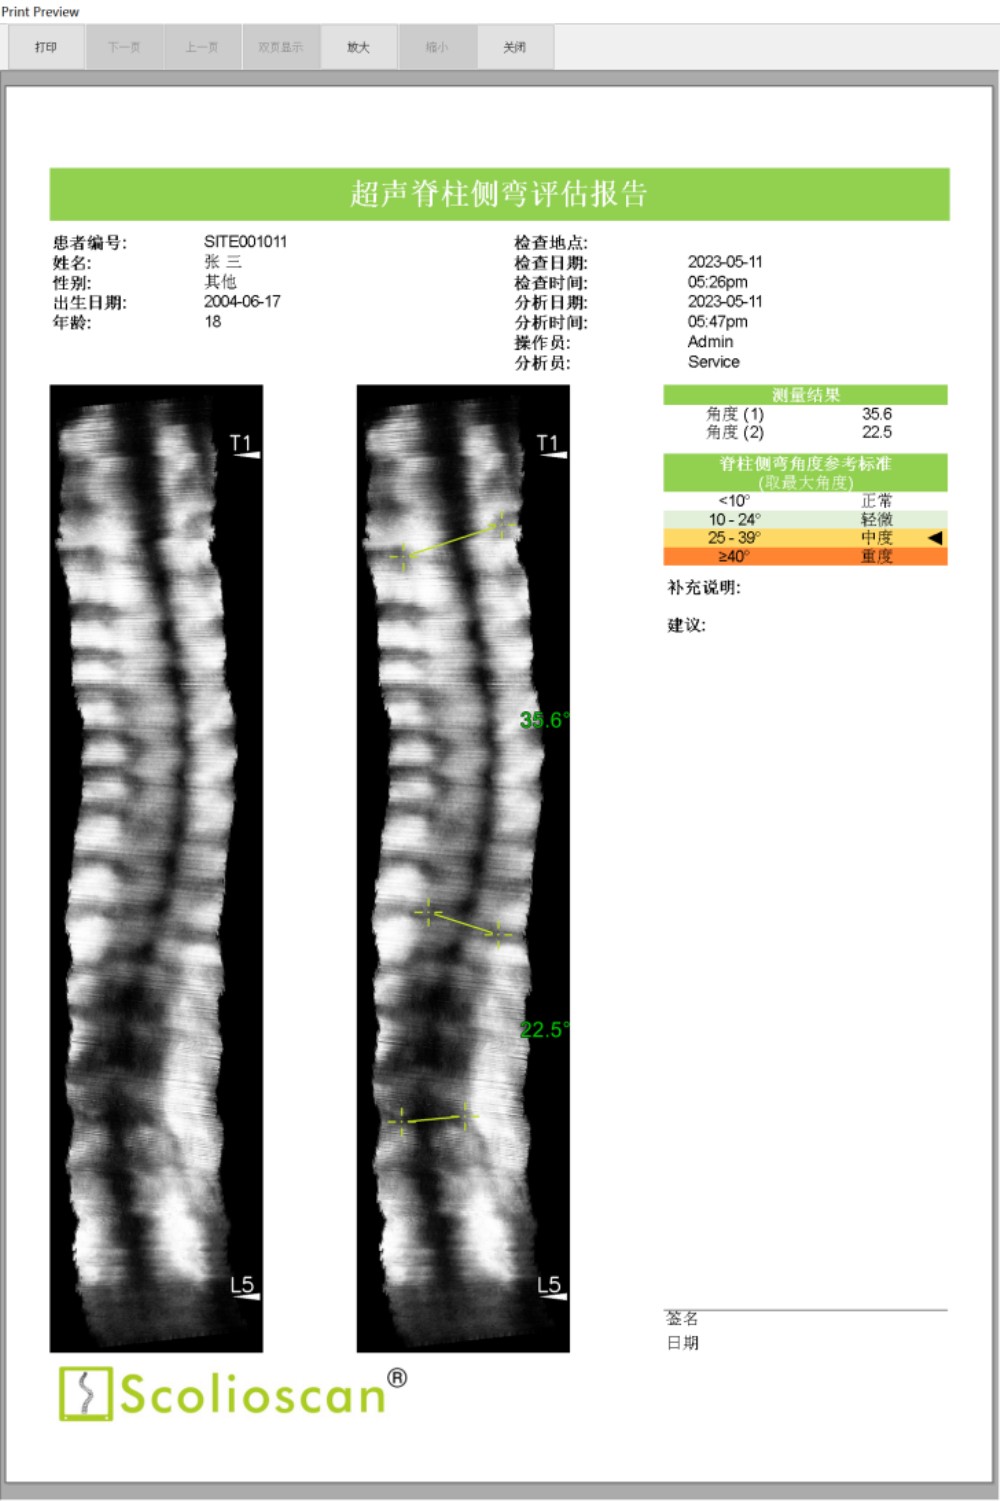

临床试验结果显示,Scolioscan®的测量结果与X光成像高度一致,线性相关度达到0.9464。使用Scolioscan®及早发现青少年的脊柱侧弯问题后,医生得以把握宝贵的黄金治疗时机,通过非手术方式有效控制和治愈疾病,实现早诊断、早治疗、早康复。

脊柱侧弯的恶化速度较快,在青春期生长突增时期,侧弯曲线以每个月1-2度的速度恶化,因此有必要对患者病情进行较为频繁的跟踪监测。脊柱侧弯患者在整个青春发育期大约需要接受10次以上的X光检查,有研究表明脊柱侧弯患者的总体癌症发病率是同龄人口的5倍。由于Scolioscan®能够避免X光辐射的风险,因此我们可以打破常规,实现安全频密的病情追踪和及时的疗效评估。

内蒙古自治区首台“Scolioscan®无辐射三维超声脊柱侧弯评估系统”成功引入我院,可广泛应用于脊柱侧弯筛查、诊断、病情跟踪和预测以及非手术治疗阶段对治疗结果的可视化反馈和评价等多个领域,为广大儿童青少年提供精准度媲美X光的无辐射、安全的脊柱侧弯评估方案,帮助患有脊柱侧弯的孩子早发现、早干预、早康复,竖起脊梁健康成长。